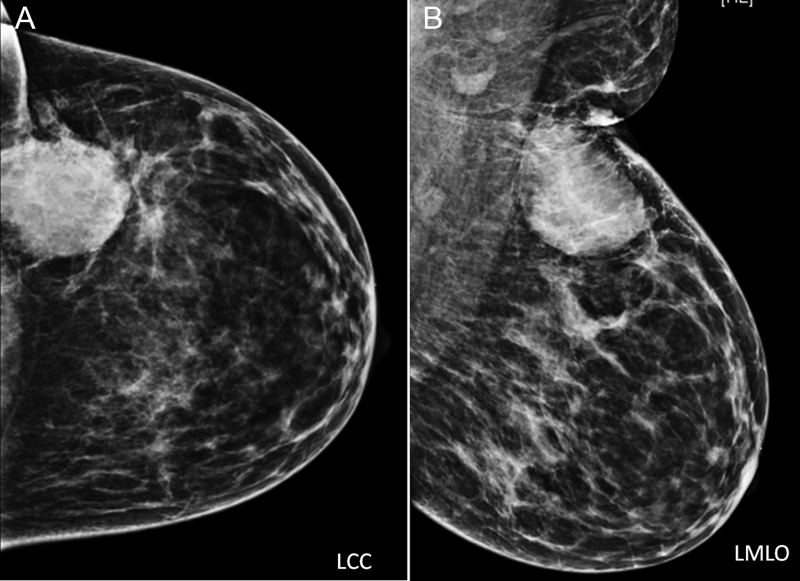

The investigation of choice is mammography. Mammography helps in the detection of breast mass along with calcifications. Various parameters about mass like shape, density, margin, any other suspicious satellite lesions, and associated features like architectural distortion, adjacent skin changes, and microcalcifications are assessed with mammograms ([Fig. 3]). At times microcalcifications extend beyond the mass, and in such cases the true extent of disease is larger than the mass or palpable abnormality seen on mammogram. Once the mammogram is evaluated, mass is further evaluated on US and appropriate breast imaging-reporting and data system (BI-RADS) category is assigned to the mass.

| Figure.3:Left breast LCC and LMLO views: showing a hyperdense mass in the upper outer quadrant of the left breast with partly circumscribed and partly indistinct margins. There is associated overlying skin thickening, better appreciated on MLO view. Few suspicious appearing left axillary lymph nodes are seen. No associated calcifications. Also, note heterogeneously dense breast parenchyma. Further evaluation with US is performed, to evaluate mass further and also look for any satellite lesion. LCC, left craniocaudal; LMLO, left mediolateral oblique; MLO, mediolateral oblique; US, ultrasound.

| Figure.3:Left breast LCC and LMLO views: showing a hyperdense mass in the upper outer quadrant of the left breast with partly circumscribed and partly indistinct margins. There is associated overlying skin thickening, better appreciated on MLO view. Few suspicious appearing left axillary lymph nodes are seen. No associated calcifications. Also, note heterogeneously dense breast parenchyma. Further evaluation with US is performed, to evaluate mass further and also look for any satellite lesion. LCC, left craniocaudal; LMLO, left mediolateral oblique; MLO, mediolateral oblique; US, ultrasound.